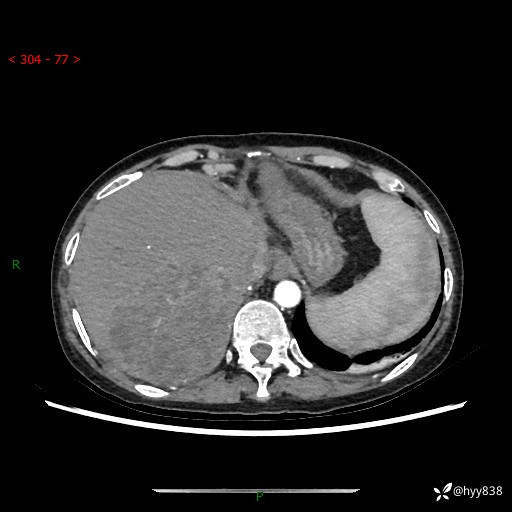

病例老年女性,发热来诊。如此“蜂窝煤”,治疗很棘手---结果公布~

性别:女

年龄:53岁

简要病史:发热(门诊急诊患者)

上腹部CT平扫